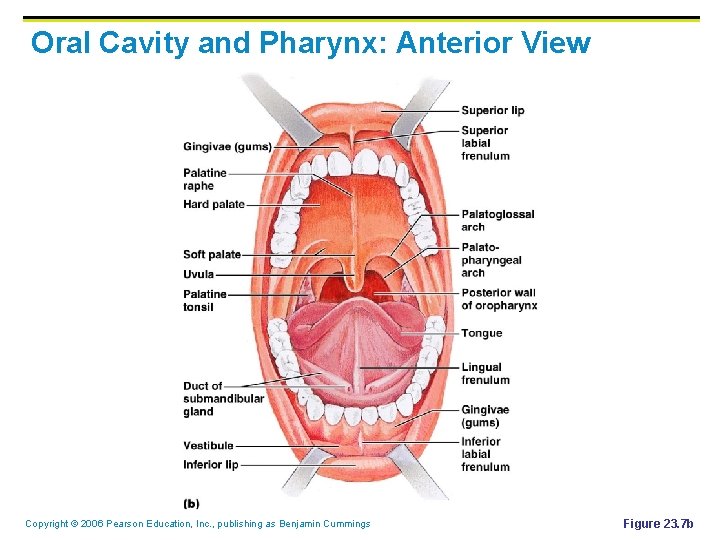

Oral Cavity and Pharynx: Anterior View Copyright © 2006 Pearson Education, Inc. , publishing as Benjamin Cummings Figure 23. 7 b